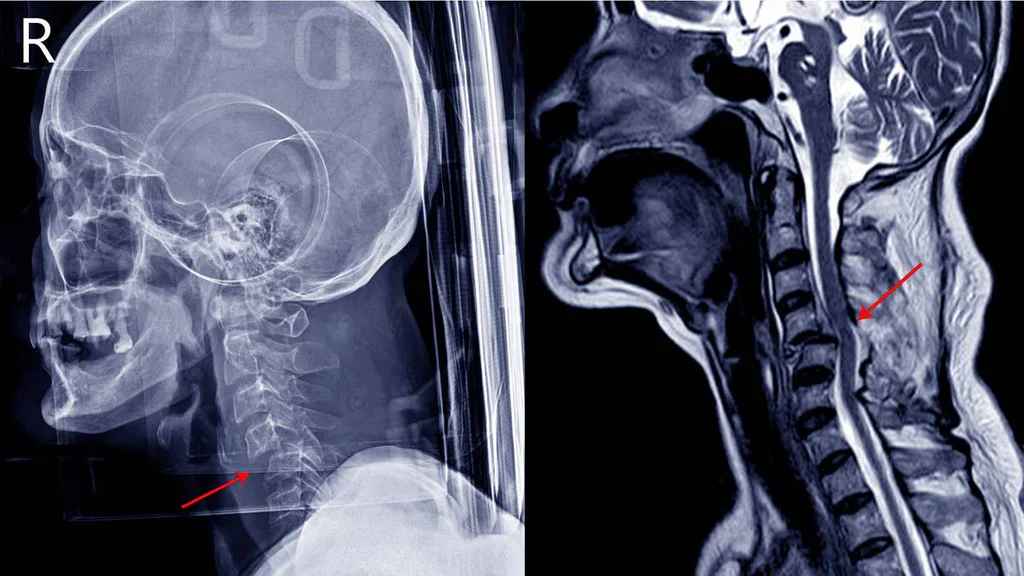

Kdyby nebylo dovedností jeho chirurga, jež mu zaživa, bez umrtvení, revolučním nástrojem i metodou odstranil z obličeje šíp vystřelený během jedné z bitev, byl by budoucí anglický a francouzský král Jindřich V. Plantagenet zemřel ve věku 16 let.